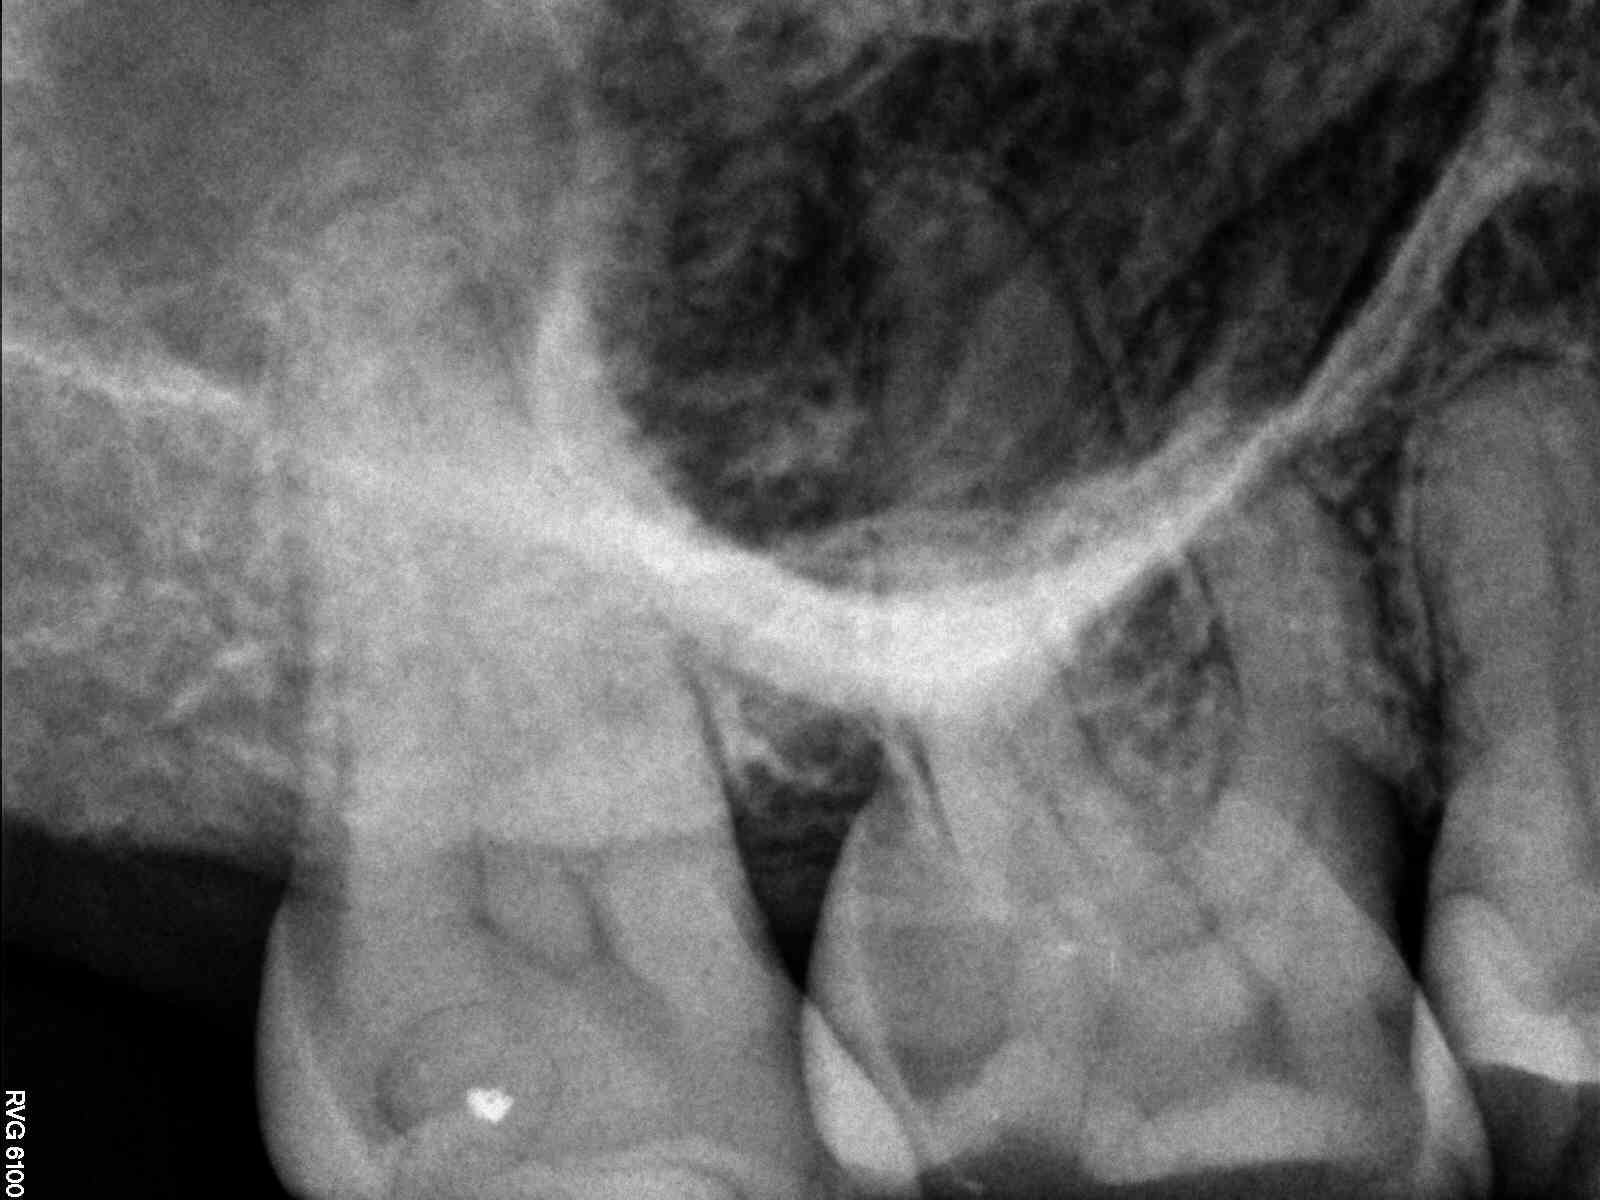

# (teeth with MB3 present- able to cleanse and shape the MB3) – (teeth

with MB2 present- able to cleanse and shape the MB2 – MB2 join

MB1 – teeth I consider calcified that no MB2 was found) – total # of 2nd

molar treated

MB2 distance from MB1 – join MB1